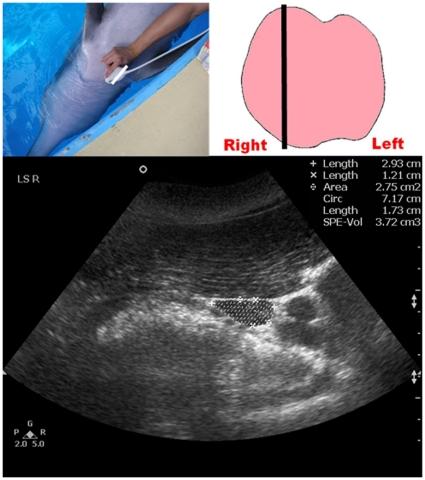

A comparison of portable ultrasound and fully-equipped clinical ultrasound unit in the thyroid size measurement of the Indo-Pacific bottlenose dolphin.

Measurement of thyroid size and volume is a useful clinical parameter in both human and veterinary medicine, particularly for diagnosing thyroid diseases and guiding corrective therapy. Procuring a fully-equipped clinical ultrasound unit (FCUS) may be difficult in most veterinary settings. The present study evaluated the inter-equipment variability in dolphin thyroid ultrasound measurements between a portable ultrasound unit (PUS) and a FCUS; for both units, repeatability was also assessed. Thyroid ultrasound examinations were performed on 15 apparently healthy bottlenose dolphins with both PUS and FCUS under identical scanning conditions. There was a high level of agreement between the two ultrasound units in dolphin thyroid measurements (ICC = 0.859-0.976). A high intra-operator repeatability in thyroid measurements was found (PUS: ICC = 0.854-0.984, FCUS: ICC = 0.709-0.954). As a conclusion, no substantial inter-equipment variability was found between PUS and FCUS in dolphin thyroid size measurements under identical scanning conditions, supporting further application of PUS for quantitative analyses of dolphin thyroid gland in both research and clinical practices at aquarium settings.

测量甲状腺大小和体积是人类和兽医医学中非常有用的临床参数,特别是用于诊断甲状腺疾病和指导矫正治疗。在大多数兽医环境中,获得功能齐全的临床超声设备(FCUS)可能较为困难。本研究评估了在便携式超声设备(PUS)和 FCUS 之间海豚甲状腺超声测量的设备间变异性;对于这两个设备,还评估了重复性。在相同的扫描条件下,对 15 只明显健康的宽吻海豚进行了 PUS 和 FCUS 的甲状腺超声检查。两种超声设备在海豚甲状腺测量方面具有高度一致性(ICC=0.859-0.976)。在甲状腺测量方面,操作员内的重复性很高(PUS:ICC=0.854-0.984,FCUS:ICC=0.709-0.954)。总之,在相同的扫描条件下,PUS 和 FCUS 之间在海豚甲状腺大小测量方面没有发现实质性的设备间变异性,支持在水族馆环境中进一步应用 PUS 进行海豚甲状腺的定量分析,无论是在研究还是临床实践中。